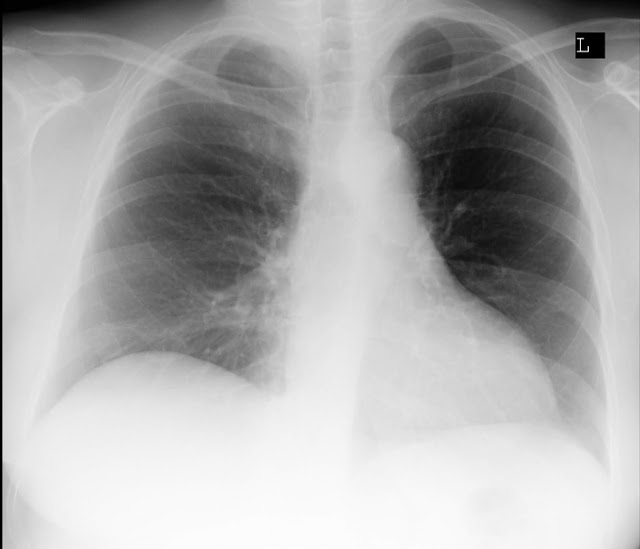

Okazało się, że prześwietlenie wykazało guz wielkości pięści

właśnie w tym prawym płucu.

Lekarze byli zdziwieni, bo w miejscu sfotografowanego guza nic

nie znaleźli.

Opisany wynik prześwietlenia nie wskazywał na żadne zmiany w

płucach to był 2011r.

3 lata temu miałam kolejne prześwietlenie tym razem z płytą.

Okazało się, że nie mam zmian w płucach.

Opisowy wynik jest już niepokojący „Pole płucne bez uchwytnych

zmian ogniskowych. Prawa wnęka zaznaczona naczyniowo. Przepona i kąty wolne;

Prawa kopuła wyżej ustawiona. Sylwetka serca w granicach normy”.